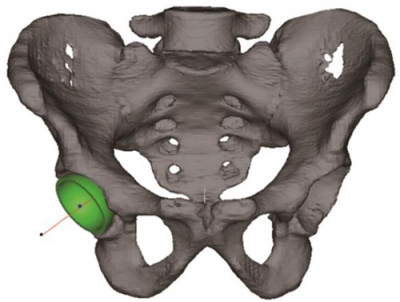

我们将CT原始断层Mask通过预处理过程获得目标的三维数字模型(STL格式),基于轮廓生长线的概念将股骨头拟合为球体,获得股骨头中心。以股骨颈的解剖轴为基准外翻后获得股骨头假体柄植入的最佳通道,建立了股骨头模板的导航管,结合股骨头颈部的反模生成了虚拟的导航模板(如图6)。

图6 连接股骨头中心和股骨近端中心线上相对较细处的一点,外翻后获得导航管位置,生成虚拟的股骨头导航模板。

我们将对照侧髋臼表面点云的最适拟合球心坐标的镜像定义为HJC。通过3-matic6.1 软件建立水平位和冠状位的辅助平面,分别获得骨盆二维平面上的投影并测量得到髋关节的旋转中心O1和髋臼的方位(如图7)。再通过三角函数的关系计算得到髋臼旋转轴上的一个点(O2)(如图8)。连接O1O2两点的直线就代表了髋臼的旋转轴,也就是模板导航管的方向,沿计算好的髋臼旋转轴植入一虚拟髋臼杯假体,可以实现三维可视化观察,判断预期臼杯植入的效果(如图9)。

图7通过骨盆冠状面、水平面两个投影平面测得髋臼方位。

图8 图中O1为髋中心,利用三角函数的关系计算得到髋臼旋转轴上的O2。

图9 将虚拟髋臼杯沿髋臼旋转轴线植入到髋臼进行模拟观察。

利用逆向技术建立与髋臼卵圆窝表面解剖形状一致的反向模板,以髋臼旋转轴线为中轴线确定导航管的方向,设计出虚拟的髋臼卵圆窝导航模板,沿导航管植入一定位针代表髋臼旋转轴,判断手术植入的效果(如图10)。